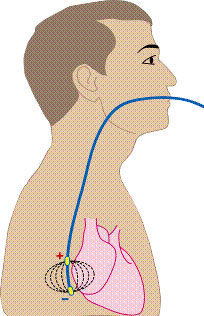

Чреспищеводная электрокардиостимуляция

Чреспищеводная электрокардиостимуляция – неинвазивная процедура, направленная на получение записи биологических потенциалов с внешней поверхности сердца, используя при этом специальный пищеводный электроды и регистрационную аппаратуру. Проведение специальных видов стимуляции для изучения электрофизиологических свойств проводящей системы, миокарда предсердий и желудочков. Выявление субстратов аритмии, их локализации и электрофизиологических характеристик. Контроль лекарственной и/или нефармакологической терапии. Ненвазивное электрофизиологическое исследование сердца (ЧПЭФИ) Опыт применения ЧПЭС в кардиологии насчитывает более 30 лет. В нашей стране первое сообщение о применении ЧПЭС у больных с ишемической болезнью сердца появилось в научной медицинской литературе более 10 лет назад. За этот период времени отношение к любому методу исследования уже носит устойчивый характер, а возможности самого метода хорошо изучены. Следует сказать, что отношение кардиологов к методу ЧПЭС в течение этого времени менялось в зависимости от развития самой кардиологии и технических возможностей применяемых стимуляторов. Повышенный интерес к этому методу в настоящее время обусловлен с одной стороны, бурным развитием самой кардиологии, как науки, в частности ее аритмологии, а также появлением современных стимуляторов с хорошими техническими характеристиками, позволяющими производить исследование с минимальными неприятными ощущениями для больного. Применение ЧПЭФИ помогает решить три основные задачи:диагностика, лечение (терапевтическое, подбор антиаритмических препаратов) и прогнозирование во многих клинических ситуациях.

- •Чреспищеводная электрокардиостимуляция